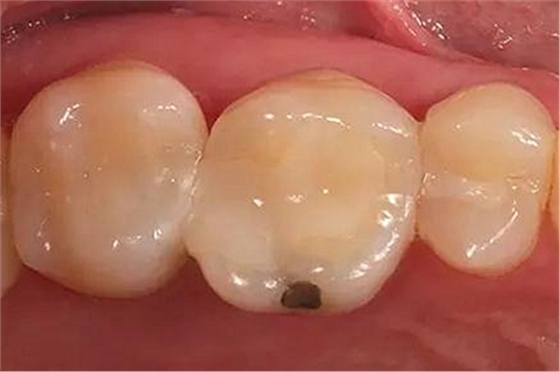

步驟1 原始狀況

16牙位牙齒牙合面觀.

牙齒經(jīng)過(guò)根管治療且充填修補(bǔ),需要重新修復(fù)。